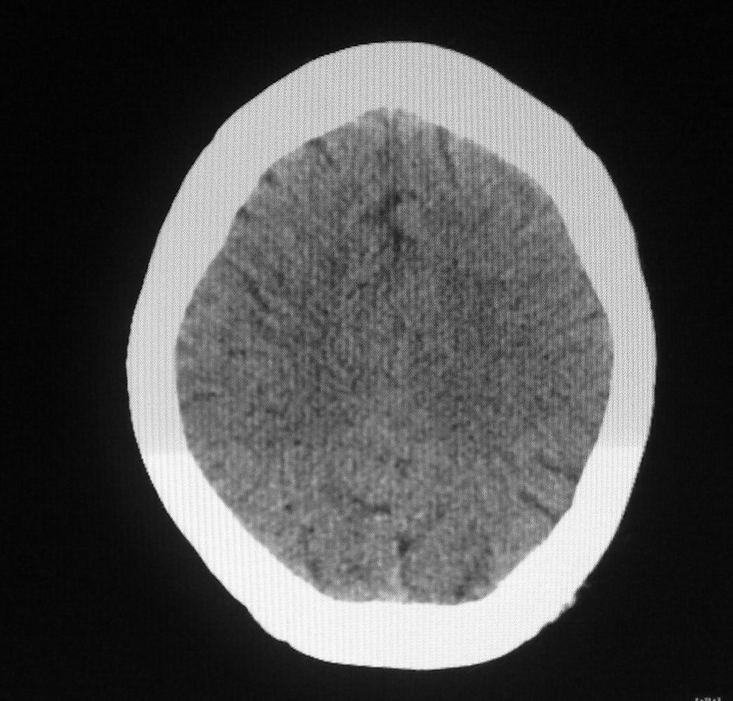

女,46岁,走路有时向一侧偏斜。是小脑萎缩吗?

小脑脑沟增多加深      为小脑萎缩引起的共济失调

小脑脑沟多于四条即为增多,又见加深,所以支持小脑萎缩。

从图像上看的确有轻度小脑萎缩征象,但患者才46岁,有外伤史吗?

小脑萎缩可能性大,建议mri检查。

小脑轻度萎缩